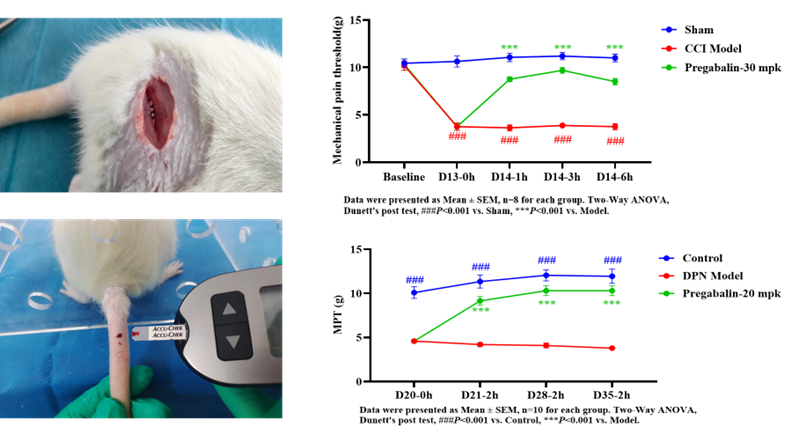

坐骨神经慢性缩窄模型(CCI) |

坐骨神经4道结扎 |

慢性束缚性损伤+炎性刺激 |

机械痛阈值 |

糖尿病外周神经痛(DPN) |

STZ诱导糖尿病 |

高血糖导致外周神经损伤 |

机械痛阈值、血糖、体重 |